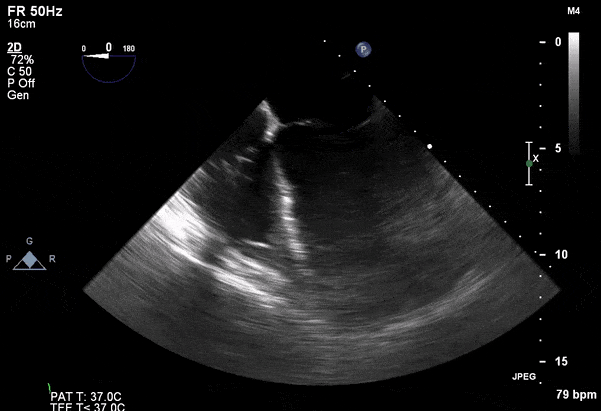

Case 2 (Pulmonic Valve IE)

Role of Echocardiography

- Echo plays an important role in the diagnosis of infective endocarditis.

- Helps identify vegetations, new valvular lesions, abscess, and other complications of endocarditis.